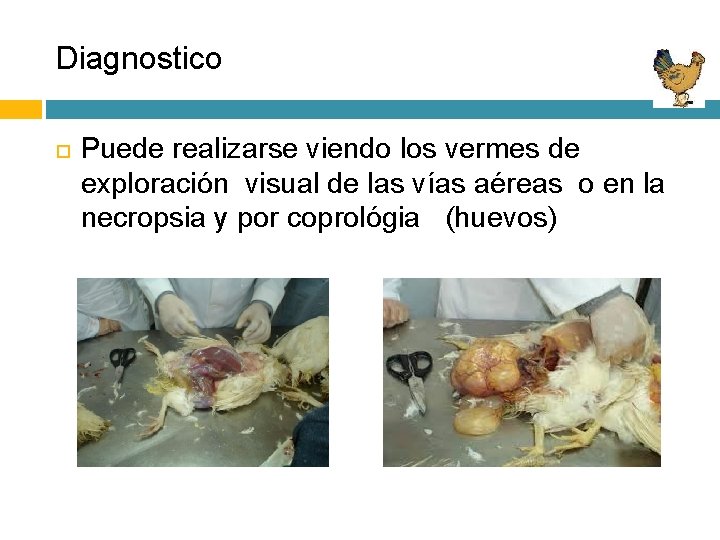

Diagnostico Puede realizarse viendo los vermes de exploración visual de las vías aéreas o en la necropsia y por coprológia (huevos)